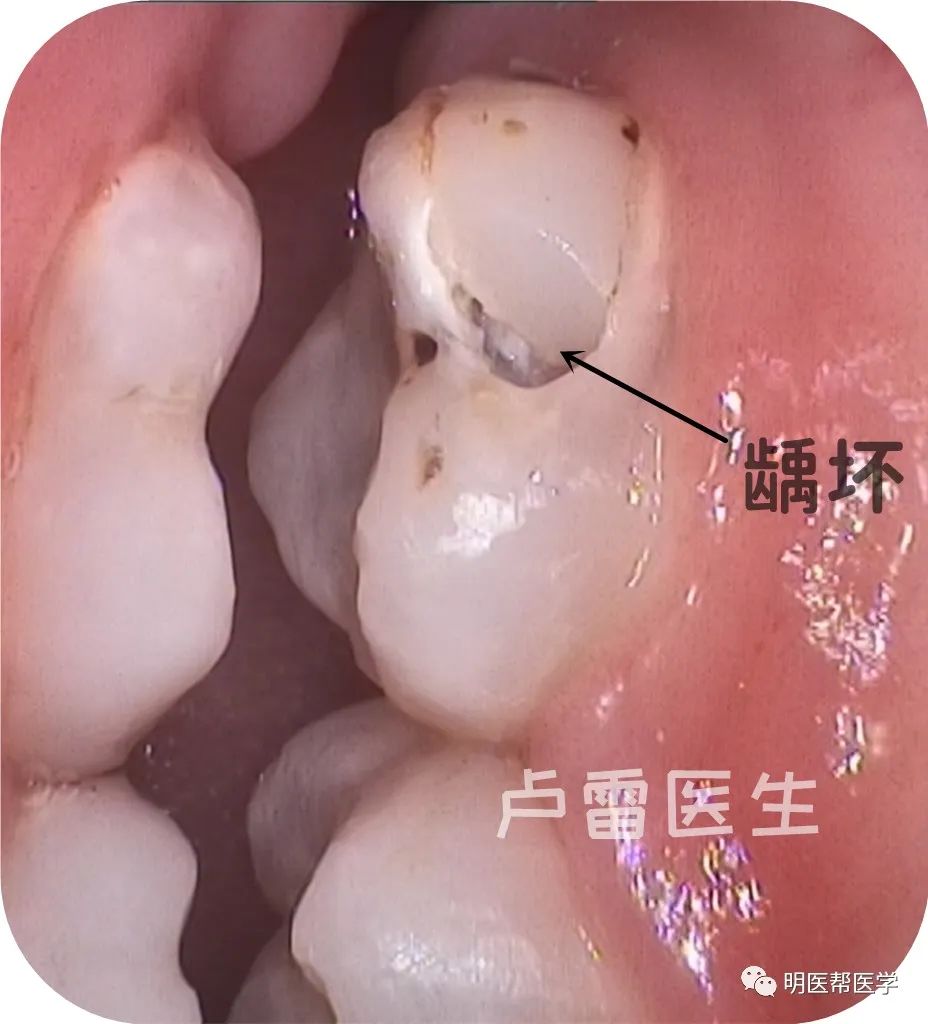

牙齿龋坏了,补牙后能用多久?

我们的牙齿龋坏,需要通过补牙阻止龋坏继续发展,所以通过补牙方式恢复牙齿外形、功能、颜色、阻止龋坏继续恶化。

卢雷医生告知您,牙齿龋洞越小,补牙后维持使用时间就越久,龋洞大则反之。